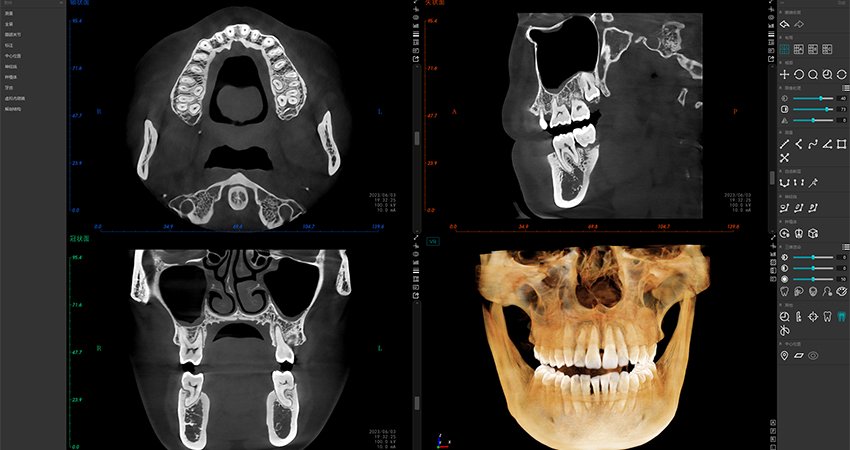

El software de diagnóstico 3D líder de Meyer y el sistema de análisis ortodóntico inteligente adoptan un diseño de UI modular, lo que hace que las funciones del software sean más cercanas a las necesidades clínicas y más fáciles de usar para los médicos, reduciendo significativamente el costo de aprendizaje.

Software de Diagnóstico 3D

MyDentViewer